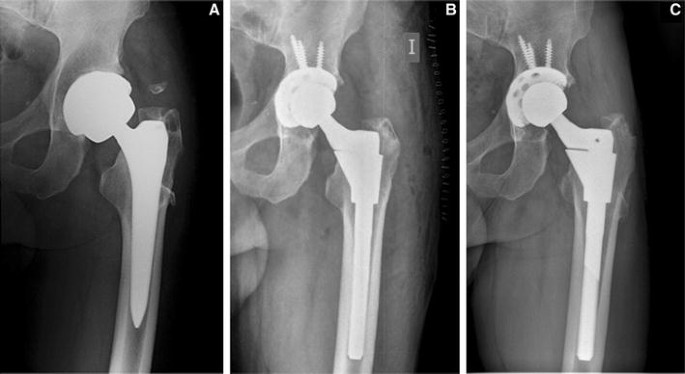

wearing out of the artificial ball-and-socket joint

dislocation (coming out of joint)